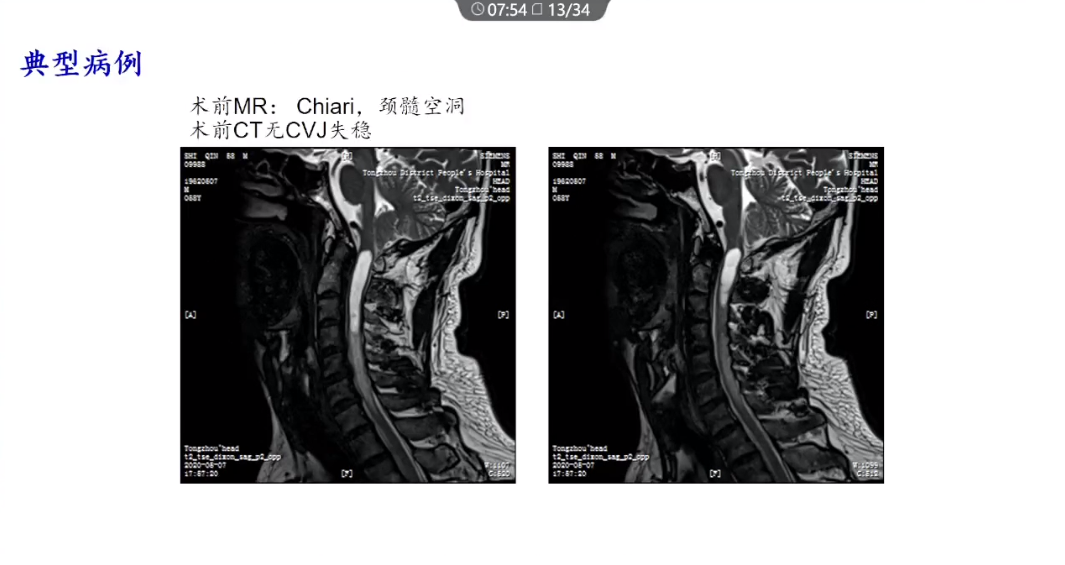

谢嵘教授:Chiari畸形的精准治疗

讲题:Chiari畸形的精准治疗